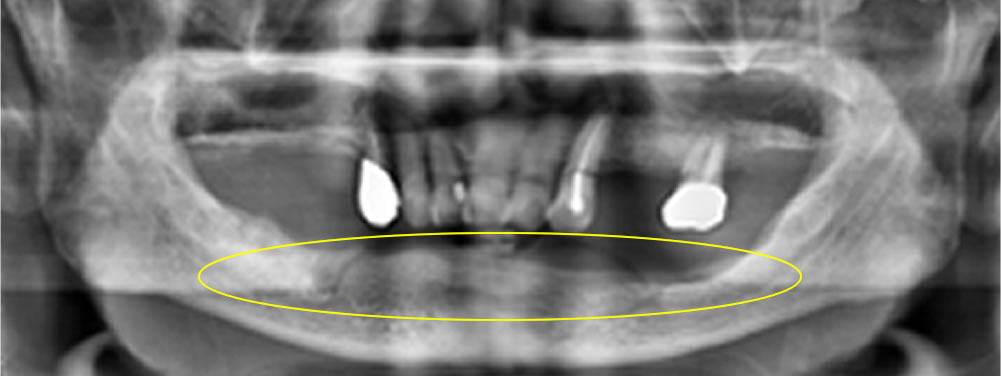

初診時のお口の状態

診察したところ、下顎の顎堤吸収(入れ歯を支える歯槽骨が痩せてしまう状態)が進行し、顎の骨の高さが全体的に低くなっていました。このような顎堤の形態では、通常の総義歯は吸着が得られにくく、義歯の安定が非常に難しい症例となります。